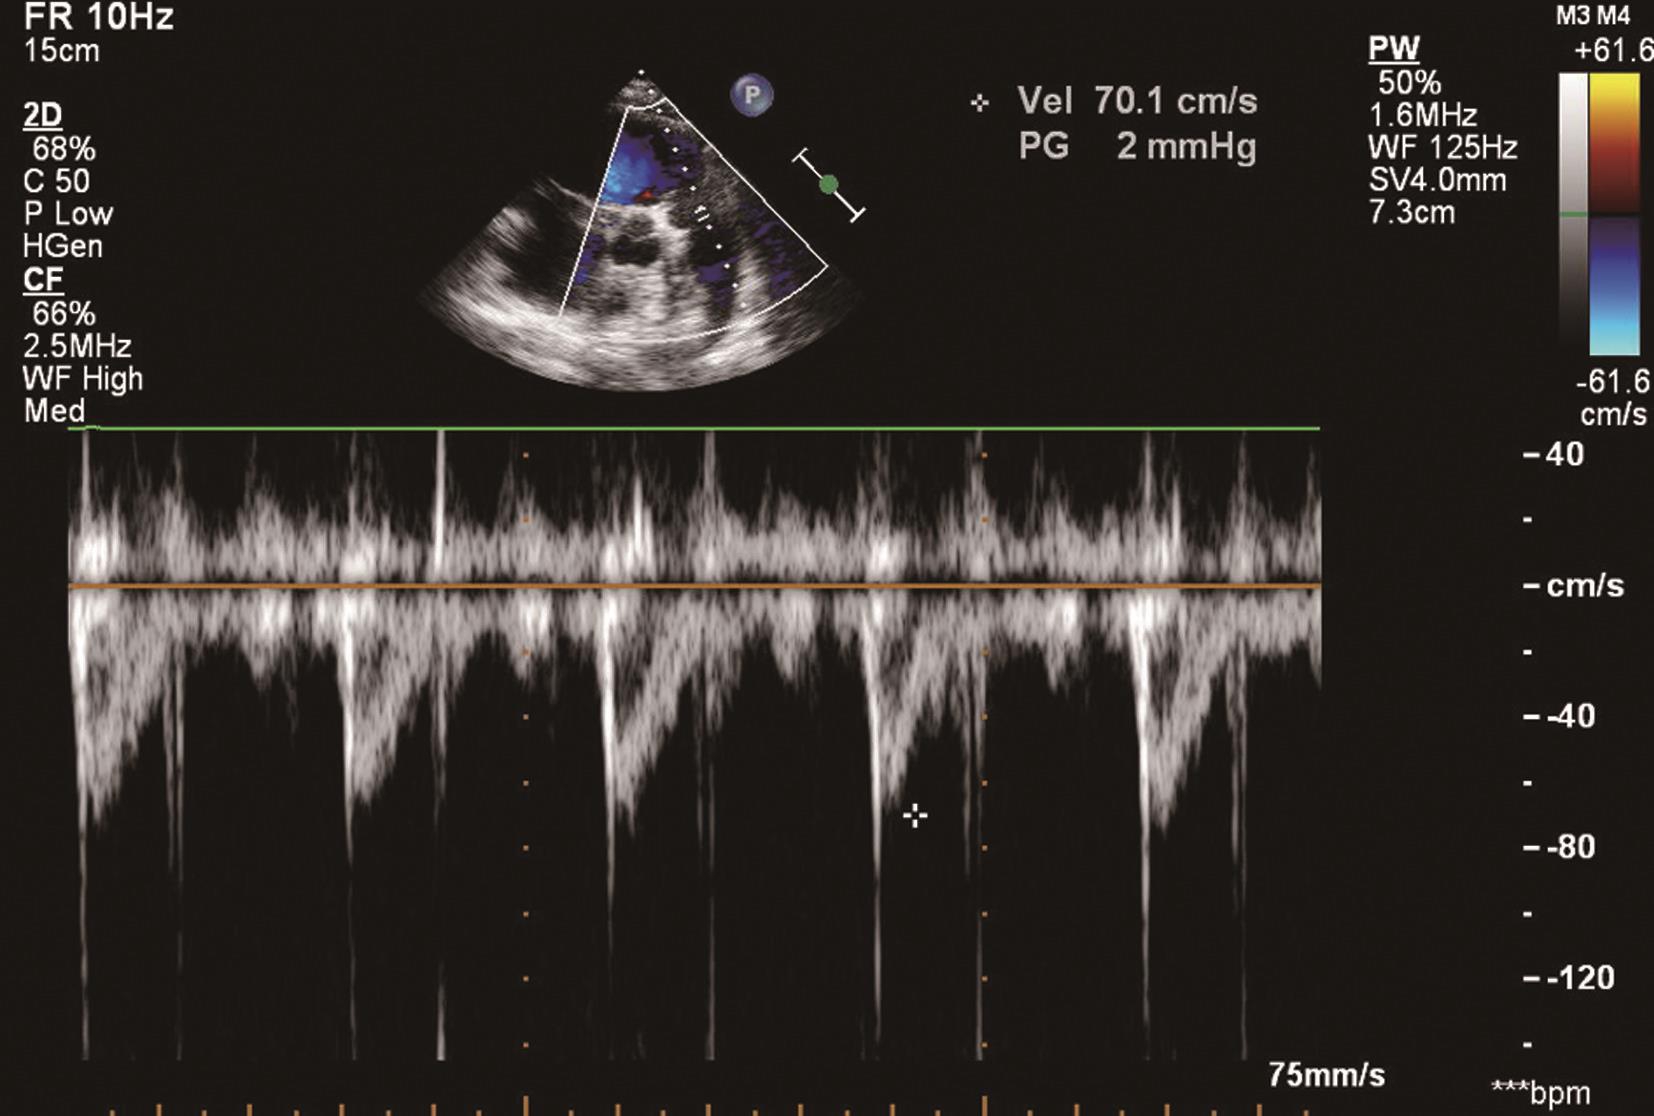

(2)大动脉短轴切面舒张期可见花彩血流信号自肺动脉经肺动脉瓣口反流入右心室流出道。连续波多普勒可探及舒张期位于基线上方的反流频谱(图6-2-3),并可测量反流的峰值流速以估测肺动脉平均压。

图6-2-3 连续波多普勒探及舒张期位于基线上方的肺动脉瓣反流频谱

PAPd=4×肺动脉瓣反流舒张末速度 2 +右心房压

PAPm=4×肺动脉瓣反流峰值速度 2

彩色多普勒检测是否存在肺动脉瓣反流,如果肺动脉瓣反流存在,再用连续多普勒测量反流速度,调整声束方向,尽量使取样线与反流束平行,以获取最大反流压差。通过肺动脉瓣舒张早期反流峰值流速及舒张末反流速度可分别估算肺动脉平均压及舒张压。